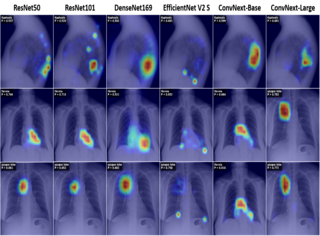

- Top 5 - CXR-LT 2026 Challenge on Long-Tailed Chest X-ray Classification Benchmark, ISBI 2026